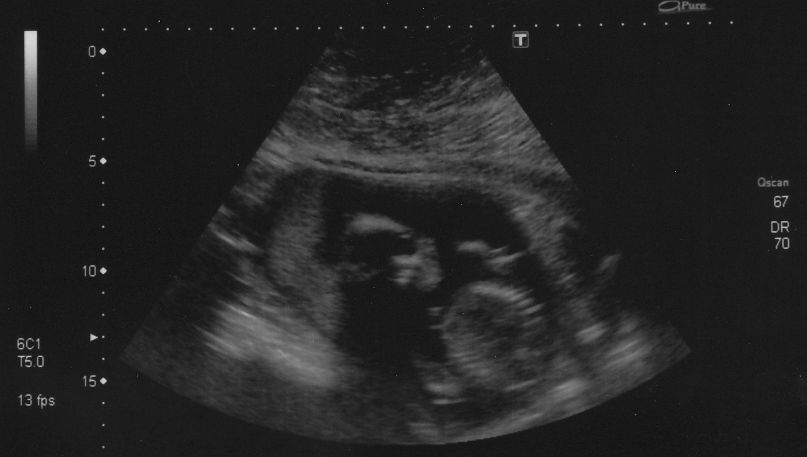

Danyoo wrote:The technician was having a hard time getting measurements because Cody was so active. "If I could just get baby to stop moving for a tenth of a second...I could measure his femur!"